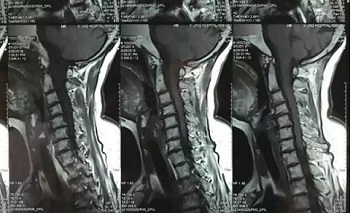

十一、将分区的磁共振图像,按顺序进行拍摄,即可获取如下比较有价值的清晰图片

(区域1)

(区域2)

(区域3)